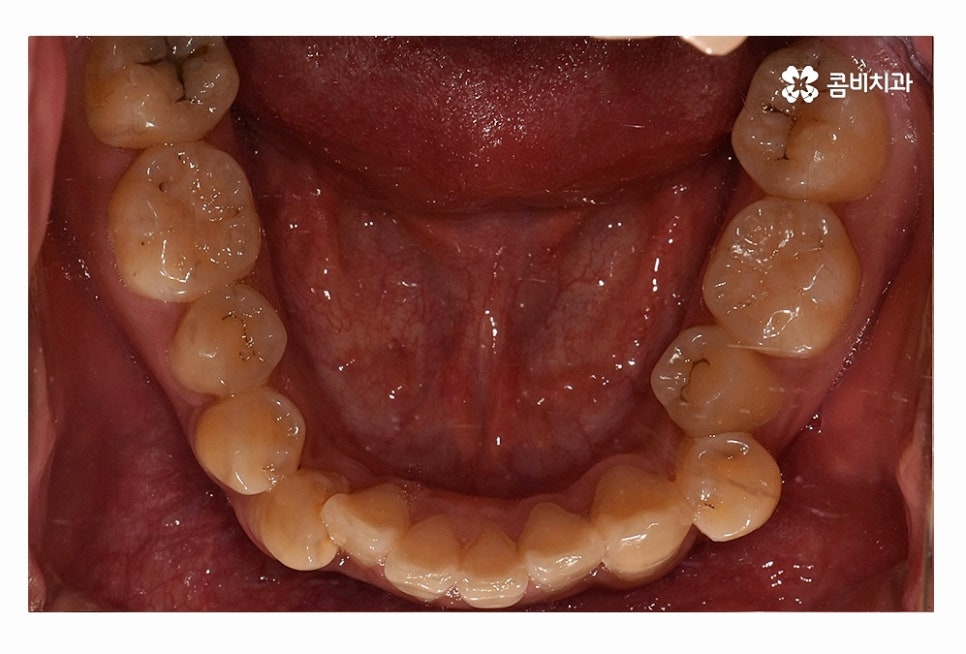

오늘 보시는 환자분의 사례처럼 덧니가 치아끼리 겹쳐 있는 경우에

치아의 이동 공간 확보를 위해서 덧니 발치 필요한 사례였으며

교합과 치아교정 후 얼굴 변화를 고려할 때도 치아교정 과정에서

발치가 필요한 사례였다고 볼 수 있어요.